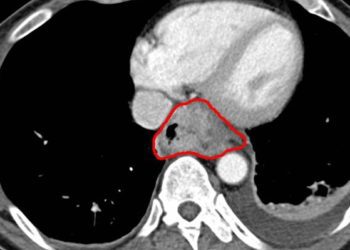

This [prospective cohort] study investigated the effectiveness of magnetic sphincter augmentation in treating gastroesophageal reflux disease (GERD). The study followed 100 GERD patients who received laparoscopic implantation of a circular magnetic device. The device augments the lower esophageal sphincter and reduces acid reflux. The study focuses on the clinical benefits of this procedure, and no control group was established.

In terms of clinical efficacy, the procedure achieved a reduction of at least 50% esophageal acid exposure in 64% of patients (95% confidence interval [CI], 54 to 73). Additionally, the procedure achieved a reduction of 50% or more in the average daily dose of proton-pump inhibitors (PPIs) in 93% of patients (95% CI, 86 to 97).

In terms of quality of life impact, the study used GERD-Health-Related Quality of Life questionnaire to quantify improvements, with a reduction of score indicating improvement. 92% (95% CI, 85 to 97) of patients had a 50% reduction in score.

In sum: This study demonstrated that magnetic augmentation of the lower esophageal sphincter could be an effective treatment for GERD. The study demonstrated both clinical reduction in acid reflux reduction and improvements in quality of life.

Due to the link between esophageal acid damage and cancer, magnetic sphincter augmentation is a novel treatment option that could reduce long term complications of GERD in patients that had only partial response to PPIs and cannot tolerate fundoplication or other surgeries.